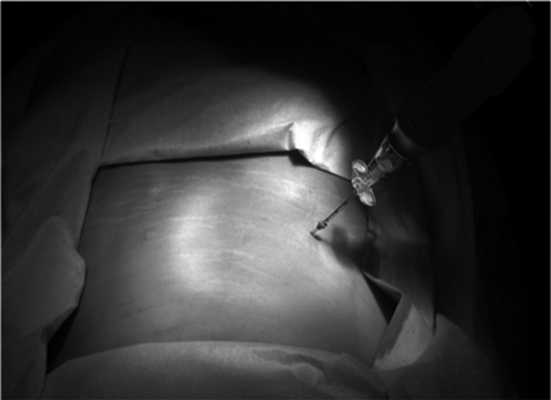

В нашей серии инвазивное крепление референсной рамки не использовалось. Референсная рамка укреплялась на стерильное операционное поле по средней линии в области поясничного отдела позвоночника или в ягодичной области на ипсилатеральной стороне доступа (рис. 3). После интеграции полученных КТ-изображений и в начале манипуляций, для предотвращения увеличения погрешности из-за смещения референсной рамки, рамку плотно фиксировали стерильной полиэтиленовой пленкой до укрепления светоотражающих шариков. Для этого использовалось стерильное полиэтиленовое поле фирмы «Opsite». После фиксации референсной рамки проводилась КТ с последующей интеграцией исследования на рабочую станцию S7, после интеграции одного из инструментов, используемых для доступа, рассчитывалась траектория проведения доступа (рис. 4).

Рис. 4. Навигационно-контролируемая перкутанная эндоскопическая дискэктомия интерламинарным доступом. а — определение места введения инструмента при помощи навигационной указки и траектории установки канюлированного эндоскопического порта; б — дилатация мягких тканей и установка канюли под контролем навигации; в — введение эндоскопа в канюлированный порт; г — изображение проекции инструмента на рабочей станции навигационной системы: синий цилиндр указывает направление и положение навигируемого инструмента; д — изображение проекции инструмента на рабочей станции навигационной системы: продолжение цилиндра желтого цвета показывает траекторию.